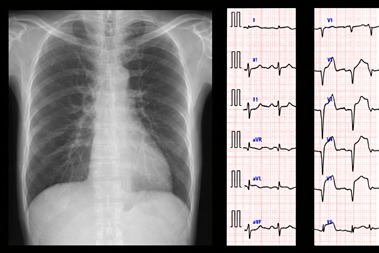

MRCP Part 1

Over 4000 MCQ with answer and tips Highly expected mock exam yearly updated...

MRCP Part 2 Written

Over 3000 MCQ with answer and explanation and tips Set of exam focused notes, f...